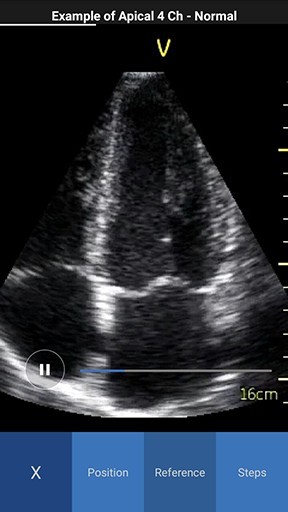

Scan Coach reference window displays with three tabs - Reference, Position and Steps.

- Reference - Provides access to multiple ultrasound image examples for normal view and a few common pathologies for the current scan plane. You can access all available reference images swiping left or right.

NOTE: By default the reference image tab is activated when you press the info icon for the first time. The white color in the image header represents an example of a normal image, while red color represents an example of a pathology image.

Reference image Normal